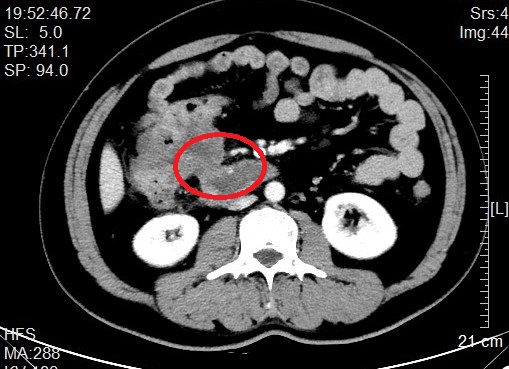

来自省内正值中年的邹先生和张先生都因“阵发性腹痛不适感”就医而发现结肠肿瘤,慕名转诊找到我院治疗。杨春康教授接诊,经过详细全面的检查后,发现二者的病情相似,都为升结肠近肝曲部的肿瘤且肿瘤已侵犯临近的重要脏器——十二指肠,全身其他部位没有发现肿瘤转移病灶,属于局部晚期病例。面对仍有治愈希望的病人以及家属的殷切希望,尽管病情高度复杂,手术风险和压力巨大,杨春康教授和他率领的医疗护理团队没有在困难面前退缩。在与病人及家属充分沟通后,决定为他们手术,并制定周密的手术方案。

杨春康主任介绍,患者的这种病情,按照目前国内多数医院的做法,大都就会直接放弃对病人的手术治疗,转而以全身化疗为主。但对于消化道的肿瘤,手术仍是目前唯一可能彻底治愈疾病的手段;此类患者要达到手术根治目的,必须做联合胰十二指肠切除的扩大右半结肠癌根治手术。一个右半结肠癌根治就已经是一个大型手术了,而胰十二指肠切除则更是一个腹部外科领域极限的特大型手术。这样的两个大型手术一起做,光光其手术的复杂性、难度系数、风险系数均是巨大的,而且术后发生包括吻合口漏在内的各种严重并发症风险极高。这既是对病人自身身体耐受能力的极限挑战,也是对主刀医生及其团队的技术、能力和医院多学科综合实力的极大挑战。如果放弃手术,病人基本难以获得较长的生存期。